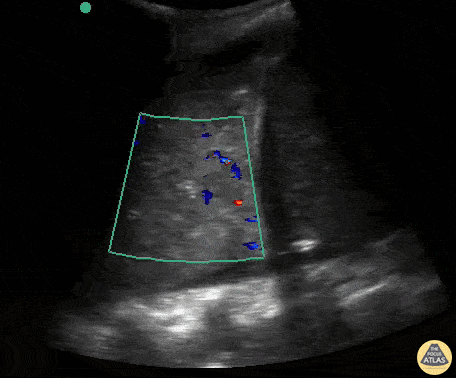

Lignes B pathologiques. Ce GIF montre la présence de nombreuses lignes B (plus de 3 par espace intercostal). Ces artéfacts verticaux, "en queue de comète", partent de la ligne pleurale et s'étendent jusqu'au bas de l'écran sans s'atténuer, effaçant les lignes A. Ils signent une perte d'aération pulmonaire